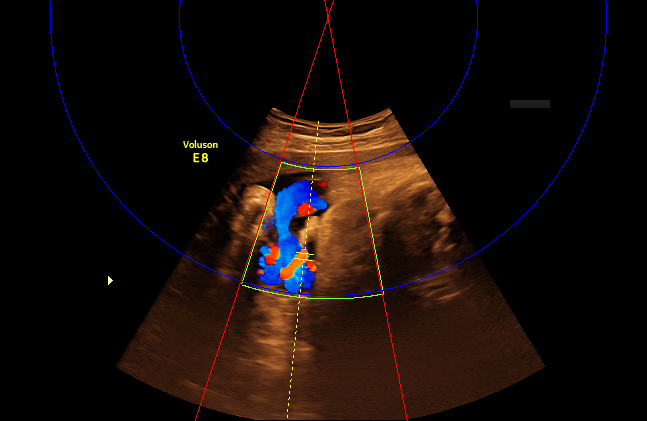

We begin with determining the direction of the ultrasound beam by utilizing the green Doppler box, which becomes active during color Doppler acquisition (see Fig. 3(a)). A binary mask of the green Doppler box is first obtained by color thresholding on the RGB pixels, followed by enhancing the mask using a watershed transform [6]. Next, a Hough line detection algorithm [1] is used to identify the two radial line segments on each side of the box. The ultrasound source is located at the intersection between the two line segments. As an extra step to prevent erroneous detection, we verify that we are able to detect the two arc lines with Hough circle detection when the center location is constrained to be at the intersection point from the previous two Hough lines (see Fig. 3(b)).

(a) Green Doppler box

(b) Detected line (red) and arc (blue)

Figure 3: Locating source of the ultrasound beam by using the green Doppler box.